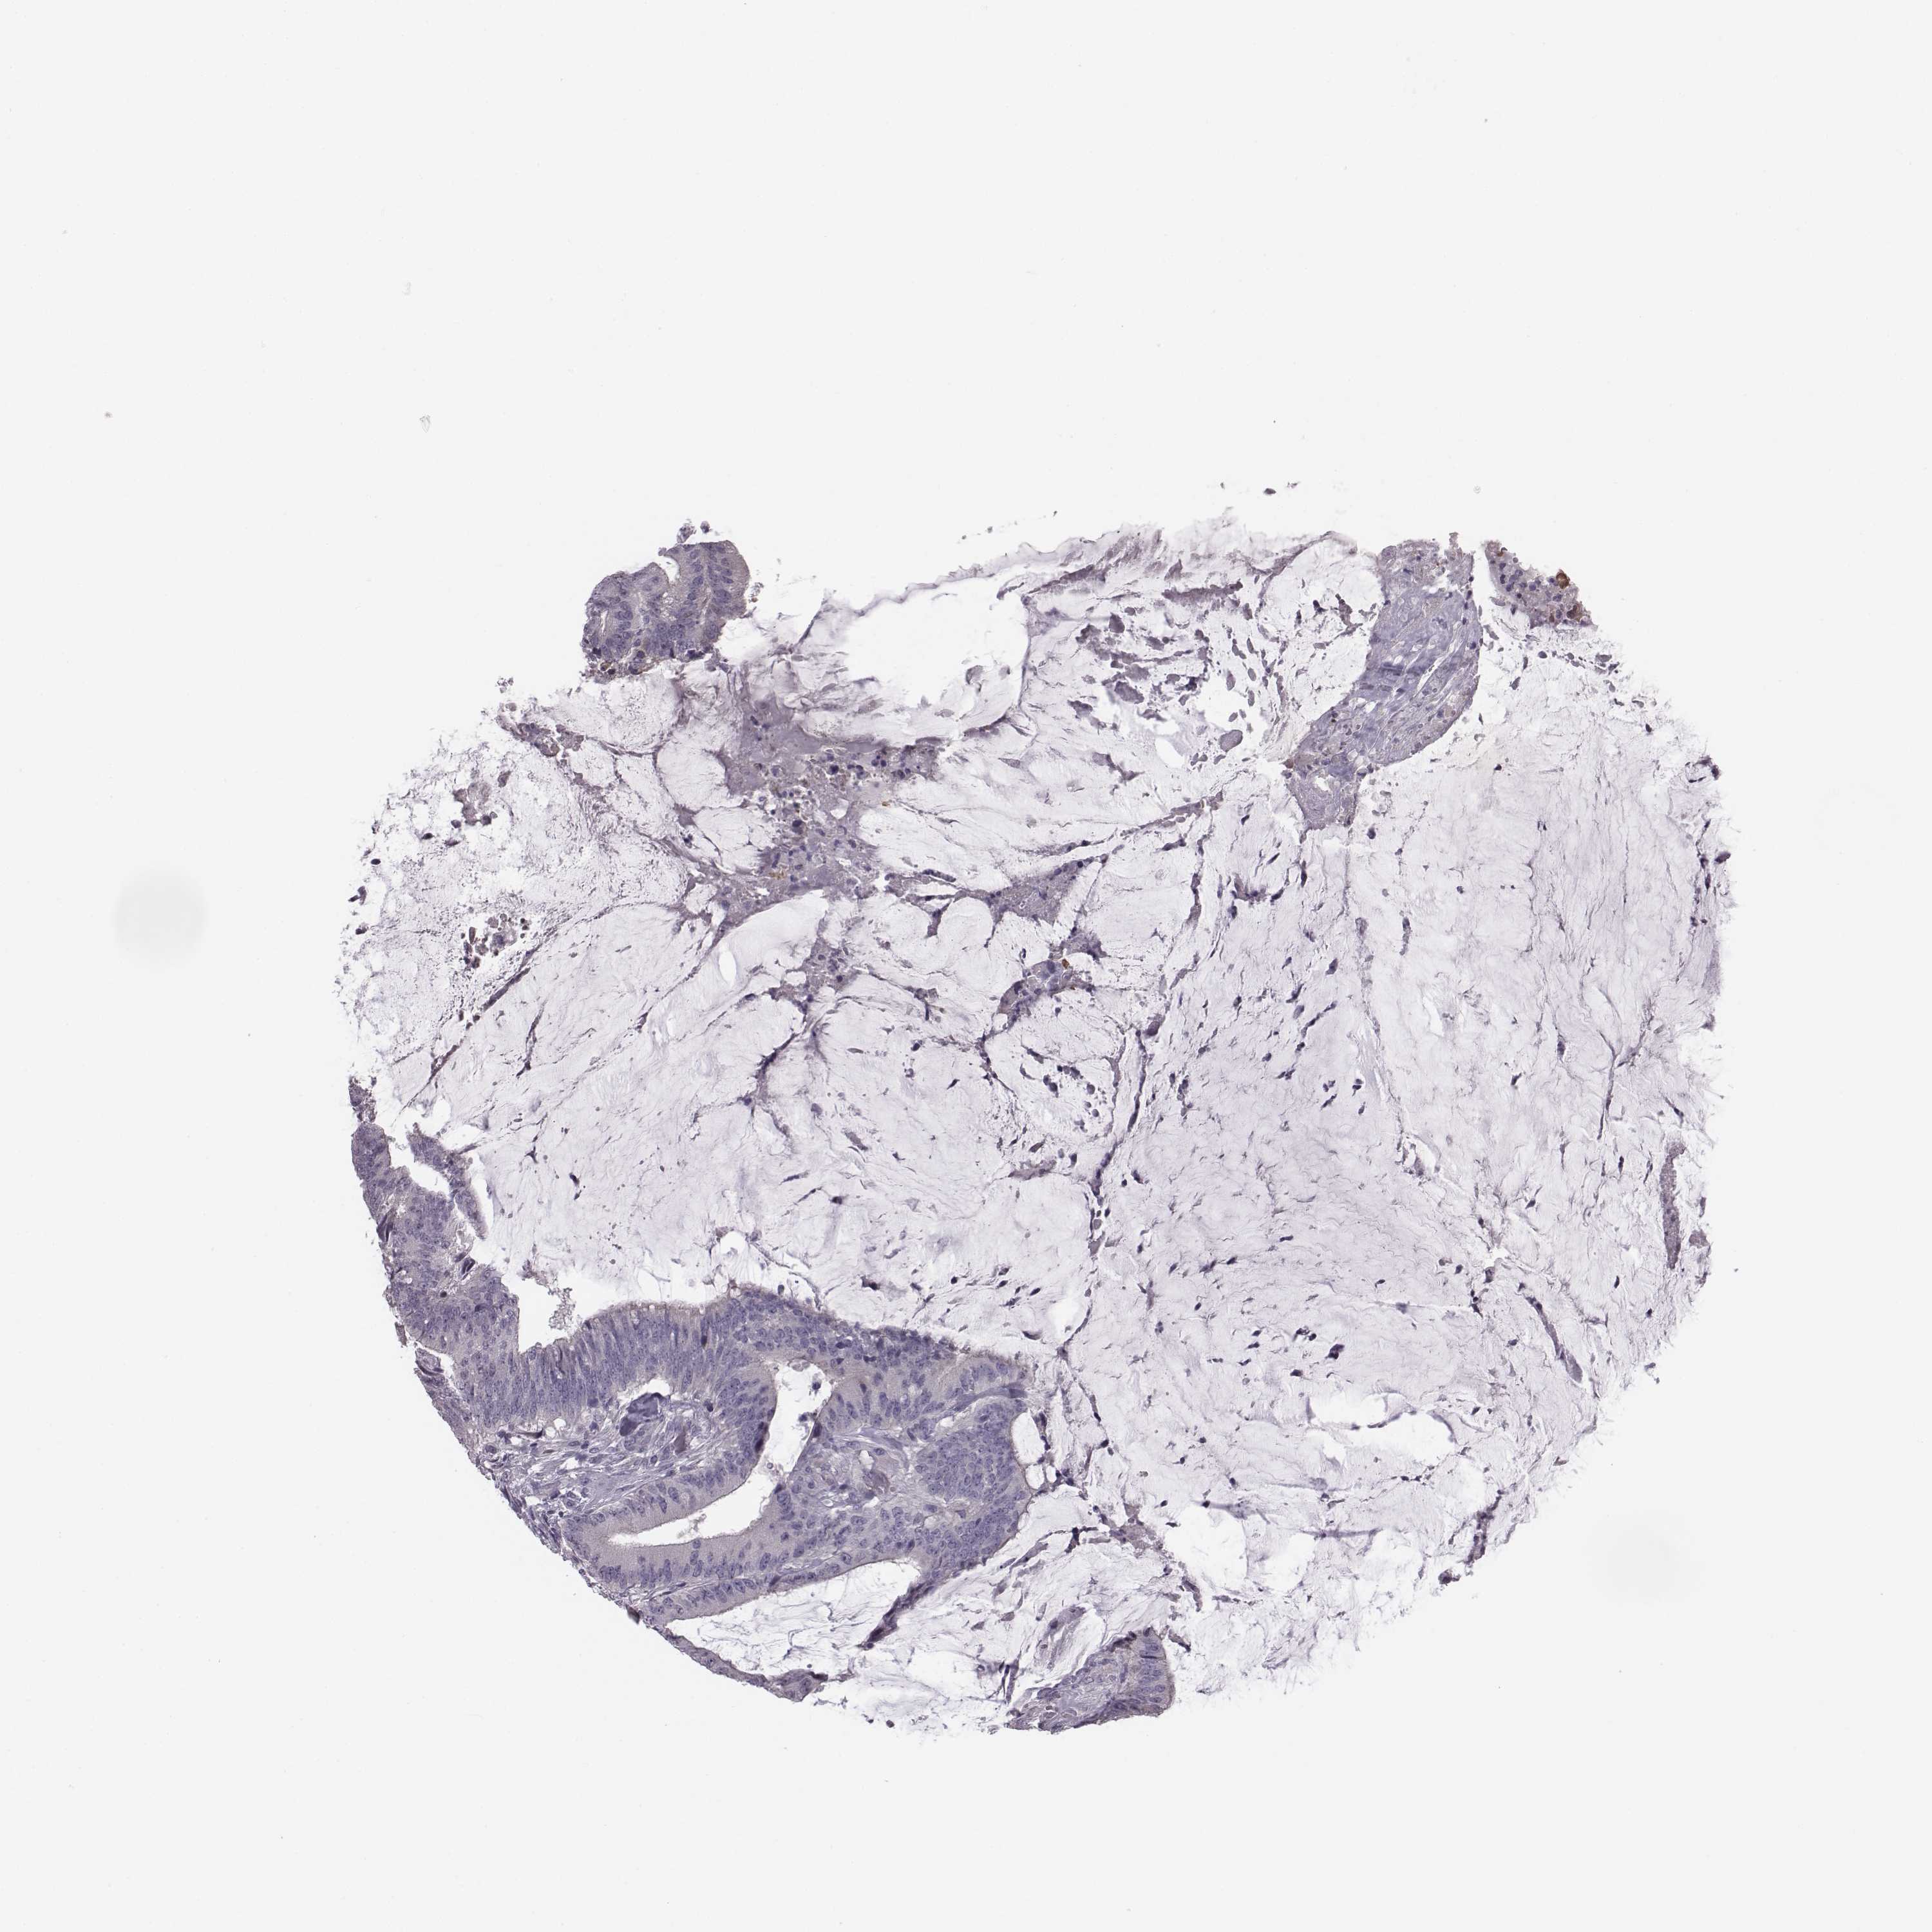

CANCER COLORECTAL CANCER Show tissue menu

Colorectal cancer

Human cancer

Colon adenocarcinoma